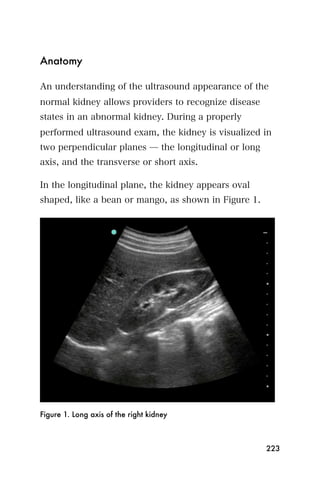

7. Freeze the image in preparation of measurement.

Using the calipers, measure the aorta from top to

bottom (anterior to posterior) including the walls ̶

248